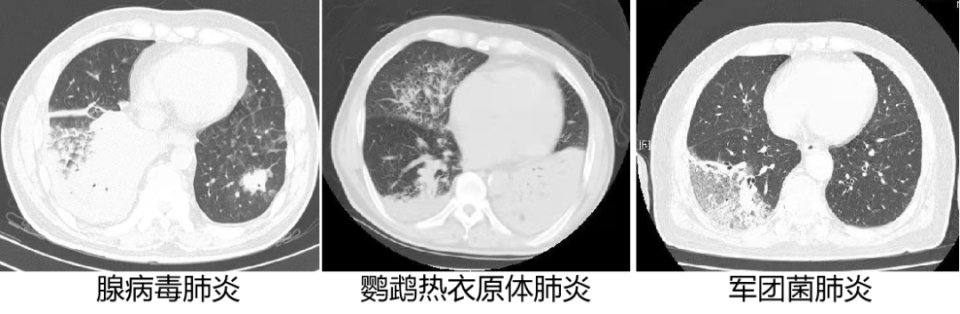

图片

肺泡性肺炎(上述 3 张图):大片实变后其他部位可以有腺泡结节,不会有树芽征,实变病灶内不会有支气管扩张。

支气管肺炎(上述 3 张图)大片实变后病灶内往往有支气管扩张,其他部位可以有树芽征、或围绕小叶中心细支气管的结节。

间质性肺炎(上述 3 张图)出现大片状阴影时,大片阴影本身不容易与另外 2 种肺炎鉴别,但磨玻璃影部分还是能够看出来是间质改变。

1. 肺泡性肺炎(大叶性肺炎):肺炎链球菌肺炎、肺炎克雷伯杆菌肺炎、军团菌肺炎及肺隐球菌病。

3. 间质性肺炎:病毒性肺炎、衣原体肺炎、立克次体肺炎(如 Q 热肺炎)、支原体肺炎、军团菌肺炎、耶氏肺孢子菌肺炎、肺双相真菌病等。